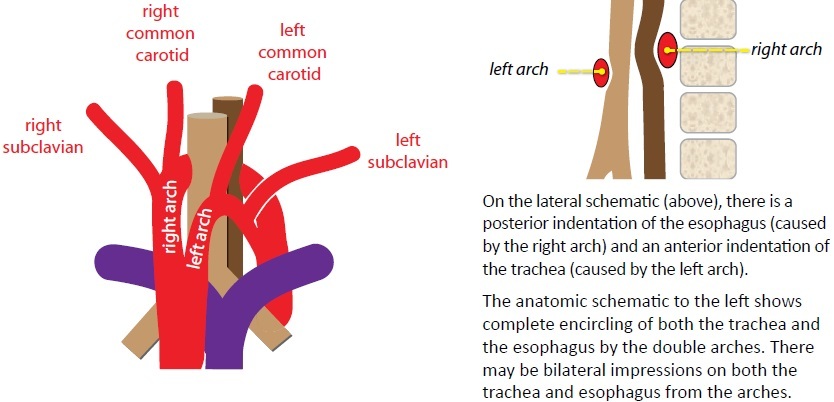

Complete encircling of the trachea and esophagus by the aortic arch or great vessels is a vascular ring.

The double aortic arch and right arch with aberrant left subclavian artery look the same on radiography/esophagram, each producing a posterior impression on the esophagus.

Double aortic arch

Double aortic arch is the most common vascular ring. The arches encircle both the trachea and esophagus, adn may cause stridor.

The right arch is usually superior and larger in caliber than the left.

For presurgical planning, the goal of the radiologist is to determine which arch is dominant, typically with MR; the surgeon will then ligate the non-dominant arch to alleviate the stridor.

Right arch with aberrant left subclavian artery

The second most common vascular ring is a right aortic arch with an aberrant left subclavian artery. The right arch indents the anterior trachea while the aberrant left subclavian artery wraps posteriorly around the esophagus. The ring is completed by the ligamentum arteriosum.

On the frontal view, a right arch with aberrant left subclavian artery produces a leftward impression/deviation of the tracea by the right aortic arch.